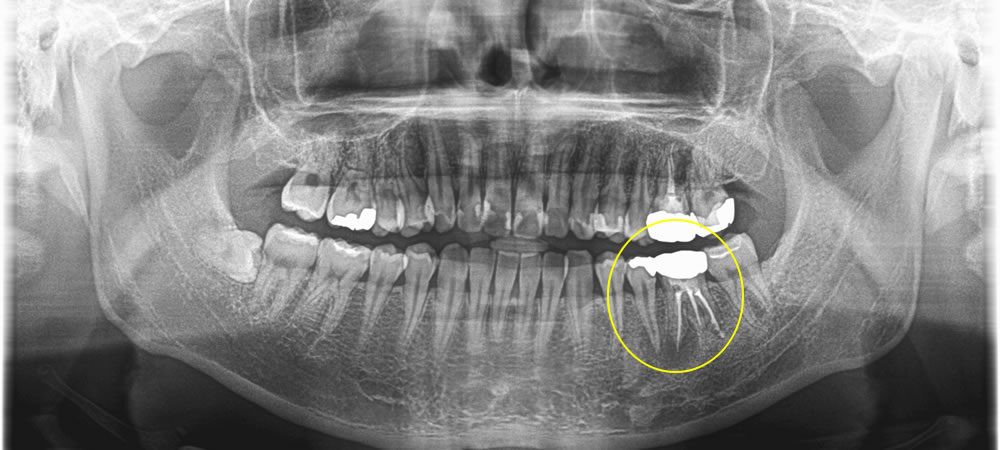

歯根破折のため抜歯しインプラントで修復した症例

年齢

40代

性別

女性